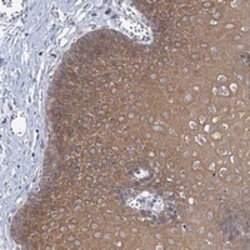

- Experimental details

- Immunohistochemical staining of human esophagus with LOC153364 polyclonal antibody (Cat # PAB23158) shows moderate cytoplasmic positivity in squamous epithelial cells at 1:20-1:50 dilution.

- Validation comment

- Immunohistochemistry (Formalin/PFA-fixed paraffin-embedded sections)